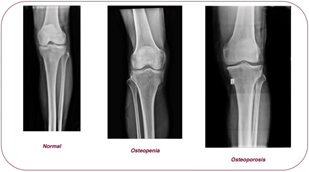

In this study, the Multi-class Knee Osteoporosis X-ray Dataset [14], available as open source, was used to automatically classify knee joint osteoporosis. The dataset consists of 1,573 knee X-ray images from different individuals and is a multi-class dataset divided into three classes: clinically normal, osteopenia, and osteoporosis (Figure 1). In this study, within the scope of binary classification, the osteopenia and osteoporosis classes were combined into a single pathological class, resulting in a total of 793 images; the normal class consists of 780 images. The images do not contain any manual annotation or regional labeling; they reflect structural changes in bone mineral density and differences in trabecular patterns, incorporating the variation in resolution, contrast, and imaging conditions encountered in actual clinical practice. In this respect, the dataset provides a highly representative and realistic resource for modeling osteoporotic changes specific to the knee region. Within the scope of the study, the dataset was used in multiple ways to evaluate different clinical decision scenarios. In binary classification experiments, the osteopenia and osteoporosis classes were combined into a single pathological class, and classification was performed against the normal class. In the ordinal classification scenario, three classes were preserved to model the natural ordinal structure of disease severity. In ensemble-based experiments, the entire dataset was used to combine representations obtained from different ViT backbones. All experiments were conducted using a k-fold cross-validation scheme that preserved the class distribution; feature selection and model training were performed only on training subsets to prevent information leakage into the test data.

Figure 1. Examples of the dataset

The X-ray images in the dataset exhibit variability in resolution and contrast levels, reflecting the imaging conditions commonly encountered in clinical practice. The images do not contain any manual markings or regional annotations, and are organized solely by class labels. This characteristic enables the dataset to be directly applicable to both traditional machine learning and deep learning–based approaches. Furthermore, the multi-class nature of the dataset provides a suitable basis for studies aimed not only at identifying advanced-stage osteoporosis, but also at distinguishing early-stage bone loss conditions such as osteopenia.